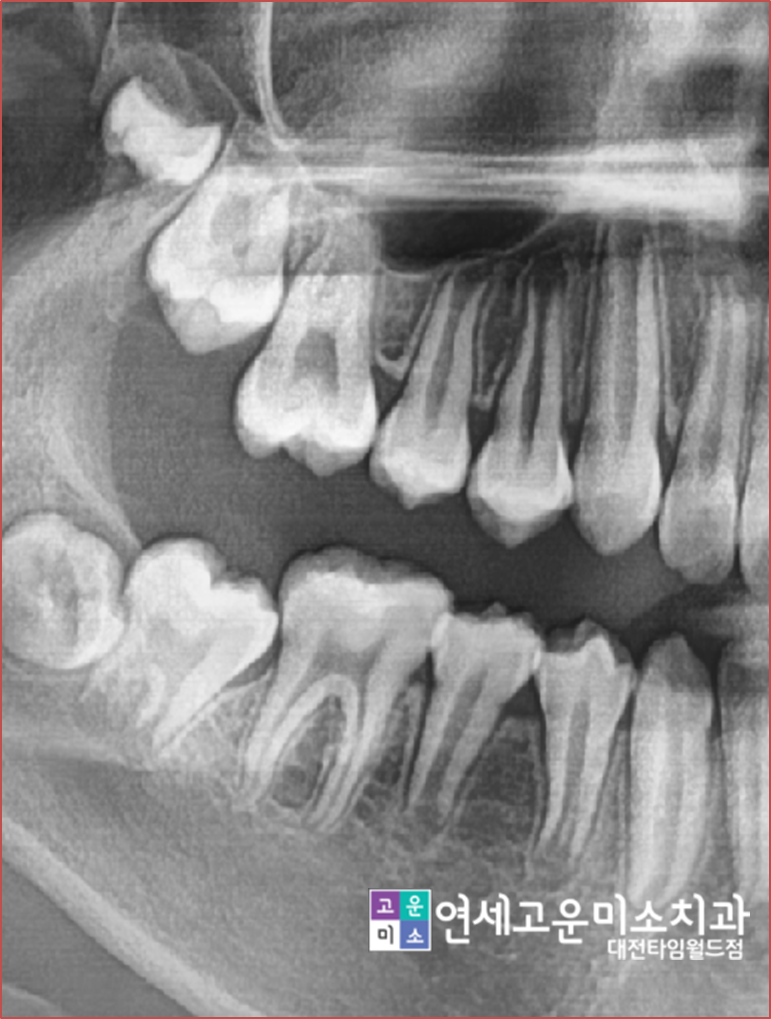

case2) 임플란트를 심어야 되는데 공간이 없어요

치아가 상실되고 나고 시간이 오래 지나면

위에 엑스레이처럼 옆에 치아가 그 공간으로 쓰러지게 됩니다.

저 상태에서는 임플란트를 할 수 없기 때문에

교정을 하지 않는다면

쓰러진 치아를 신경치료를 하고 씌운 뒤

임플란트를 하게 됩니다.

-->하지만 이렇게 치료를 하면

건전한 치아를 삭제해야 하는 단점이 생기고

쓰러진 채로 임플란트를 하기 때문에

음식물도 잘 낍니다.

이런 경우 간단한 부분교정을 통해서

쓰러진 치아를 세우고

공간을 확보한 후

임플란트를 심을 수 있습니다.

case3) 영구치가 못 올라와요

어린이 환자분들 경우에

영구치가 못 올라오는 경우가 종종 있습니다

저렇게 되는 대표적인 이유가 "이소맹출"이라고

해서 영구치가 잘못된 위치로 맹출 하여 다른 영구치가

맹출 하는 것을 방해하는 경우입니다.

위에 엑스레이도 보면 큰 어금니가 앞으로 쓰러져서

나오면서 앞에 작은 어금니 나오는 공간을 점유했습니다.

이런 경우 그냥 방치가 되면 공간은

점점 없어지게 되고, 결국에는

발치교정을 해야 되는 경우가 발생합니다.

이 환자분은 간단하게 저 부위만 부분교정을 해서

앞으로 쓰러진 영구치를 원래 제 위치로 보내고

작은 어금니가 날 공간을 확보하는 작업을 시작하였습니다.